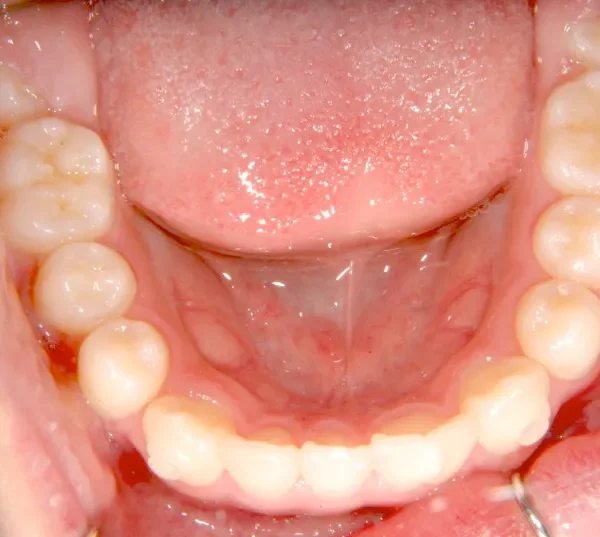

上下の歯並びが狭く、永久歯の生える隙間がありません。

右下に癒合歯があり 上下の歯並びのアーチが悪くなっています。

オリジナルの着け外しのできる装置で治療しました。

治療回数○回、4年7ヶ月の治療期間で矯正治療を終了しました。

1期治療で十分な結果が得られたと思います。